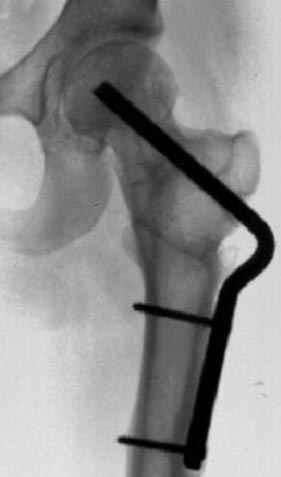

Несколько снимков из моей коллекции, чтобы разьяснить, почему мы до сих пор делаем различные варианты остеотомии.

На рисунке N1 предоперационный план лечения ложного сустава шейки бедра- линия ложного сустава, угол и направление введения импланта, клиновидная остеотомия в градусах и миллиметрах, второй снимок после коррекции, расчет, на сколько удлиняется конечность и размеры импланта;

N3 рисунок окончательный снимок, после операции моя рентгенограмма должен выглядеть примерно как эта картина. На N4 снимке клин перед удалением; N5 послеоперации 3 нед.; N6 окончательная рентгенограмма.

варус при проксимальном отделе 95 градусной пластиной.

Отправитель: Djoldas Kuldjanov 23 Ноябрь 2004, 18:21

пластическая модель; и коррекция бедра аппаратом Илизарова.